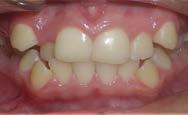

Paciente femenina de 15 años de edad que acudió a la Clínica de Ortodoncia Instituto Profesional Odontológico Contemporáneo (IPOC) en Saltillo, Coahuila, México. El motivo de su consulta fue que “quiero brackets porque sus colmillos están encimados”. Los estudios de rutina le fueron solicitados en la historia clínica SDCP. A la inspección clínica se observó paciente mesofacial, forma facial ovalada, con lado de compresión del lado derecho y lado de distracción del lado izquierdo, perfil recto, línea media facial y dental inferior no coincidían, tercio inferior aumentado, labios medianos e incompetencia labial (Figura 1).

El examen clínico intraoral reveló una clase I molar bilateral, caninos superiores en infraoclusión, por ende la clase canina no se puede clasificar, presencia de apiñamiento severo, rotaciones en premolares superiores e inferiores, línea media inferior desviada hacia el lado derecho 3.5 mm,

Figura 1. Paciente femenina 15 años de edad.

falta de coordinación de las arcadas, el arco inferior con forma cuadrada y el superior forma ovoide, el overjet de 2 mm y el overbite de 2 mm (Figura 2).

Figura 2. Fotografías intraorales iniciales.